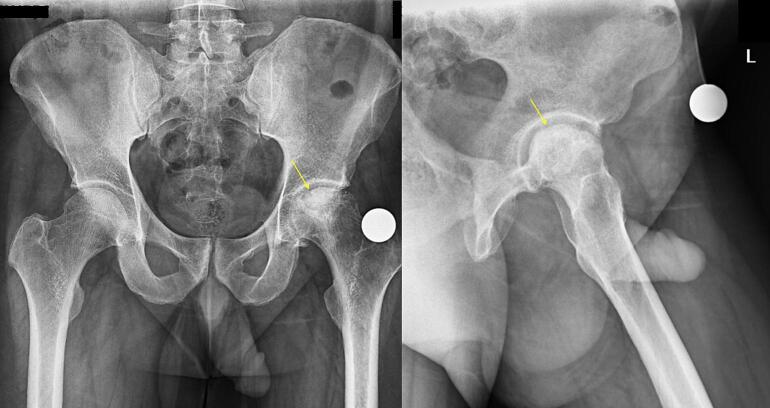

Case presentation: A 44-year-old male with femoral head avascular necrosis underwent left total hip arthroplasty. An epidural catheter was placed at the L2/3 level for postoperative pain management without complications. Two days postoperatively, the patient developed right-sided femoral nerve palsy. MRI scans revealed no spinal cord compression or hematoma. The patient's neurological symptoms began to improve five days after surgery and fully resolved by the eighth postoperative day without intervention.

Clinical discussion: Femoral nerve palsy following epidural anesthesia is exceedingly rare and has not been previously documented. Differential diagnoses, including spinal hematoma and nerve compression, were excluded through comprehensive imaging. The transient nature of the palsy suggests a potential mechanical factor related to epidural catheter placement, such as catheter twisting or transient nerve irritation.